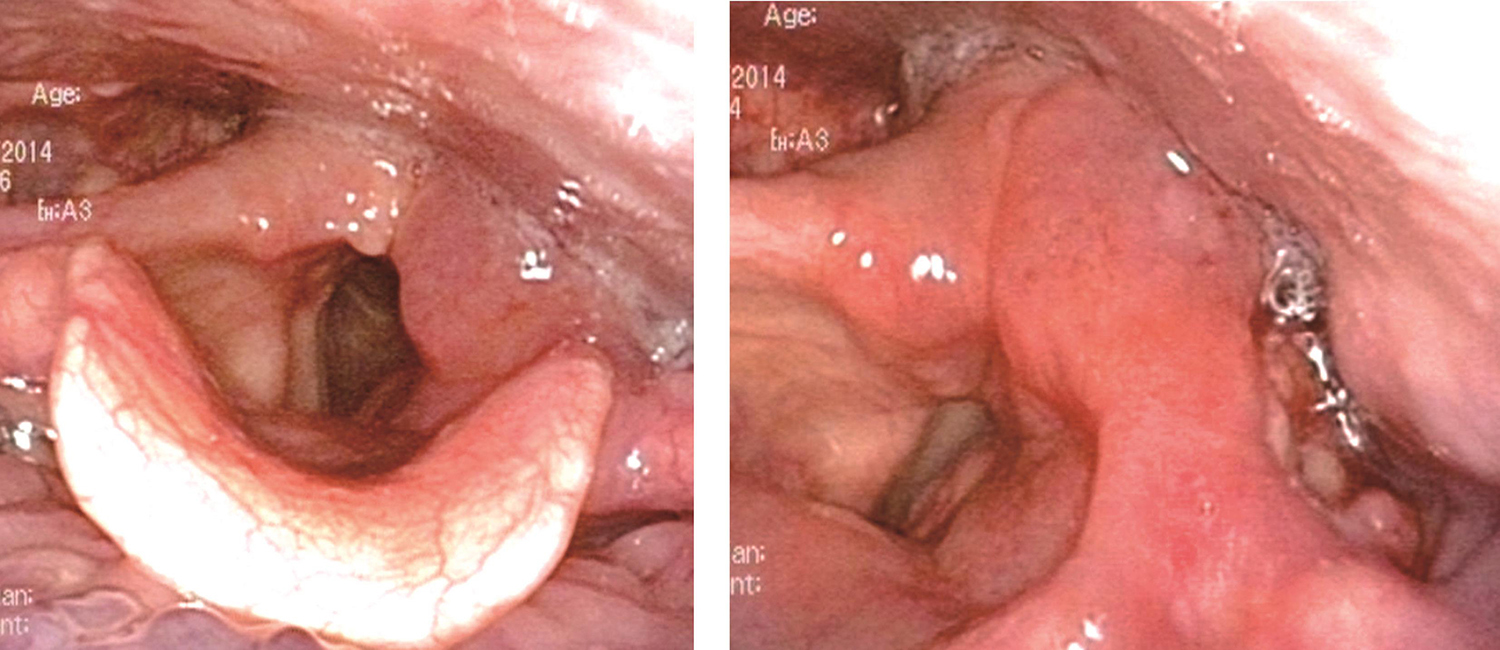

1.2014年12月1日电子喉镜检查 鼻咽部黏膜光滑,未见明显异常。口咽双侧扁桃体未见肿大。舌根部淋巴滤泡略增生。左侧梨状窝内侧壁灰白色粗糙新生物,杓会厌皱襞肿胀,黏膜光滑,向下未累及梨状窝尖。环后区及杓间区黏膜光滑,喉内结构正常,黏膜光滑,双侧声带活动正常(图1)。

图1左侧梨状窝内侧壁灰白色粗糙新生物

内镜诊断:下咽癌(梨状窝区T2)。